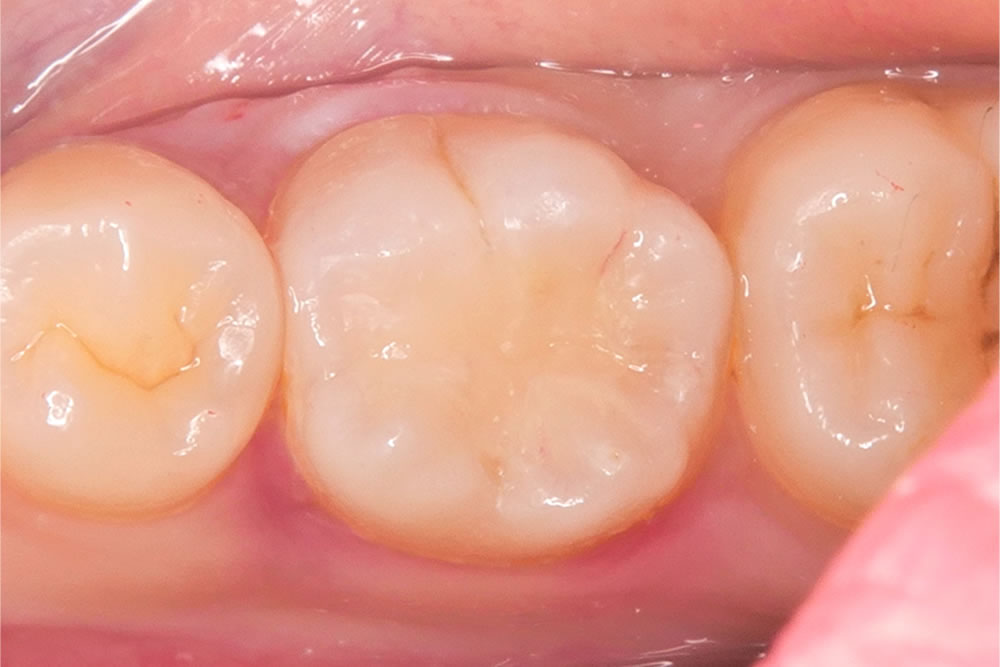

治療完了

形態修正と研磨を行い、治療が終わりました。

治療前後の比較